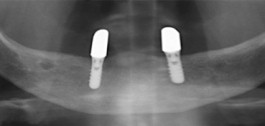

Implantation / Implantate

Vor nicht allzu langer Zeit bedeutete Zahnverlust häufig das Tragen von Teil- oder Vollprothesen. Die Praxis bietet mit dem Tätigkeitsschwerpunkt Implantologie den dauerhaft festsitzenden Zahnersatz für verloren gegangene Zähne.

Implantate sind künstliche, meist schraubenförmige Zahnwurzeln aus Titan oder Zirkondioxid und bieten das Fundament für einen stabilen Zahnersatz im Ober- beziehungsweise Unterkiefer. Reintitan und Zirkondioxid sind biokompatible Werkstoffe. Sie lösen in der Regel keine Allergien aus.

Zahnimplantate sind in der Regel zwischen 6 und 14 mm lang und haben einen Durchmesser von etwa 3 bis 6 mm. Dadurch, dass ein Implantat fest in den Kieferknochen einwächst, ist die Verankerung so fest wie bei einem gesunden eigenen Zahn.

Schema eines Zahnimplantats mit Implantatkrone, Implantatkörper, Zahnfleisch und Kieferknochen

Einsatzgebiete von Implantaten:

• Einzelzahnersatz mit Erhalt gesunder eigener Zähne, ohne Abschleifen

• Versorgung großer Zahnlücken mit festen Brücken durch Pfeilervermehrung

• Vermeidung herausnehmbaren Zahnersatzes

• Fester Halt für abnehmbaren Zahnersatz

Vorgang

Bevor ein oder mehrere Zahnimplantate gesetzt werden können, müssen Zähne und Zahnfleisch in Ordnung sein. Um beurteilen zu können, ob ein Zahnimplantat eingesetzt werden kann, ist eine umfangreiche Diagnose notwendig.